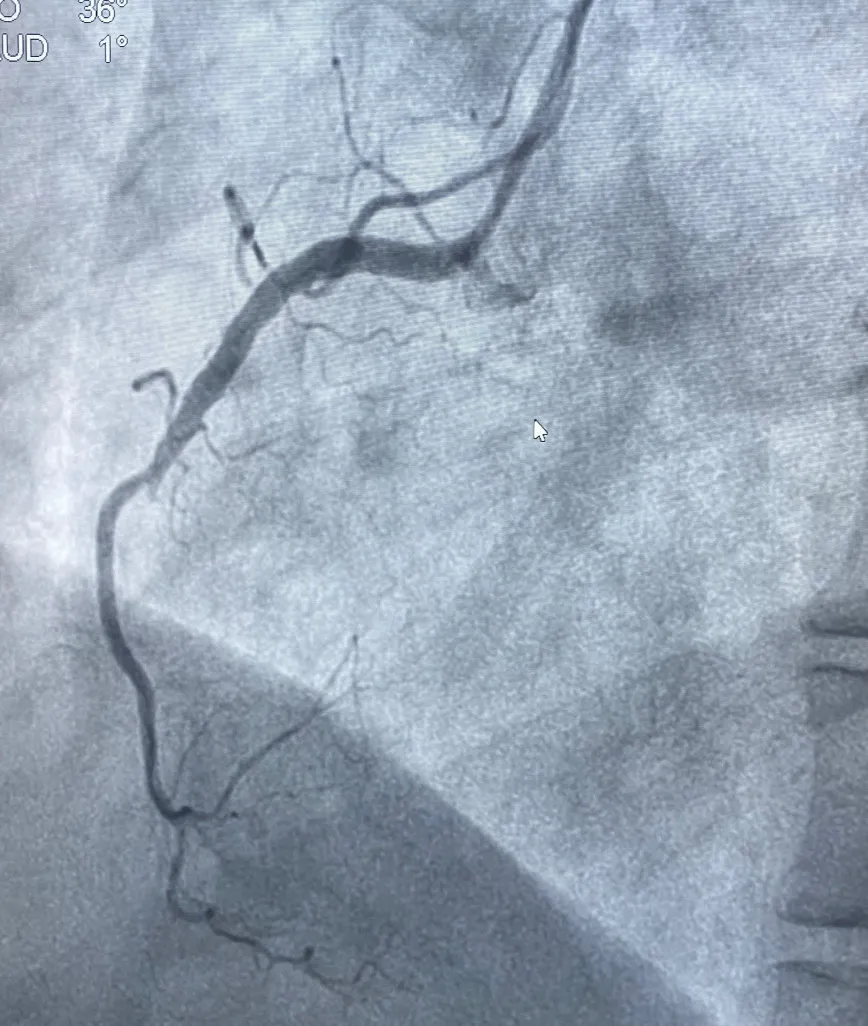

术前右冠中段完全闭塞